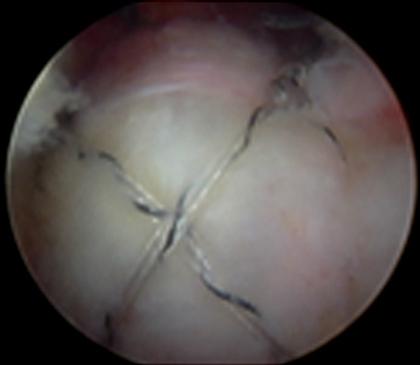

การรักษาโดยการผ่าตัดผ่านกล้องไหล่ ถือเป็นมาตรฐานการรักษาโรคของข้อไหล่ที่ยอมรับกันทั่วโลก นอกจากสามารถให้การวินิจฉัยแล้วยังเป็นการรักษาในคราวเดียวกัน กรณีที่เหมาะสมต่อการผ่าตัดส่องกล้องข้อไหล่ คือโรคของข้อไหล่ที่รักษาด้วยวิธีอนุรักษ์นิยมอย่างเต็มที่แล้ว ซึ่งประกอบด้วย การรับประทานยาแก้ปวด เช่น พาราเซตามอล, ยาลดอาการอักเสบที่ไม่ใช่สเตียรอยด์ และยาคลายกล้ามเนื้อ ร่วมกับกายภาพบำบัดอย่างเต็มที่แล้วไม่ได้ผล เป็นเวลาอย่างน้อย 3-6 เดือน จึงพิจารณานำวีธีการผ่าตัดผ่านกล้องมารักษา ซึ่งจะทำการเปิดแผลขนาด 0.5 - 1 ซ.ม. ประมาณ 2-3 แผล เพื่อใส่กล้องขนาดประมาณ 4 มิลลิเมตร ใส่น้ำเกลือเข้าไปในข้อเพื่อขยายพื้นที่ในการผ่าตัด และใส่อุปกรณ์การผ่าตัดเพื่อทำการรักษา พบว่าผลการรักษาไม่แตกต่างจากการรักษาโดยการเปิดแผล แต่กลับฟื้นตัวได้เร็วขึ้น

ตัวอย่างการผ่าตัดผ่านกล้องรักษากระดูกงอกทับเส้นเอ็นหัวไหล่